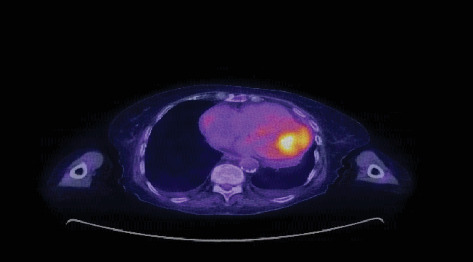

Background: Cardiac metastases, though more common than primary cardiac tumors, remain under-recognized due to their often subtle clinical presentation. These tumors can lead to life-threatening complications, and their diagnosis is typically delayed. Objective: This paper is aimed at reviewing two distinct cases of metastatic cardiac tumors, shedding light on diagnostic challenges, clinical presentations, and management approaches. Methods: We present two cases of patients with metastatic melanoma and undifferentiated malignant spindle cell neoplasm, respectively. Diagnostic imaging, including echocardiography and PET scans, was used to identify the cardiac masses, and biopsy results provided histopathological confirmation. Treatment plans involved systemic immunotherapy, chemotherapy, and surgical resection. Results: In both cases, cardiac metastases were detected through advanced imaging, despite the patients presenting with nonspecific symptoms like abdominal pain and shortness of breath. The metastatic tumor in one patient responded to immunotherapy before surgical excision, while the other patient, in advanced stages, opted for supportive care. Conclusion: Cardiac metastasis should be considered in cancer patients who present with unexplained cardiac symptoms. A multidisciplinary approach, including imaging and biopsy, is crucial for accurate diagnosis. Despite aggressive treatment, the prognosis remains poor, emphasizing the need for early detection and better therapeutic strategies.

Abstract Image